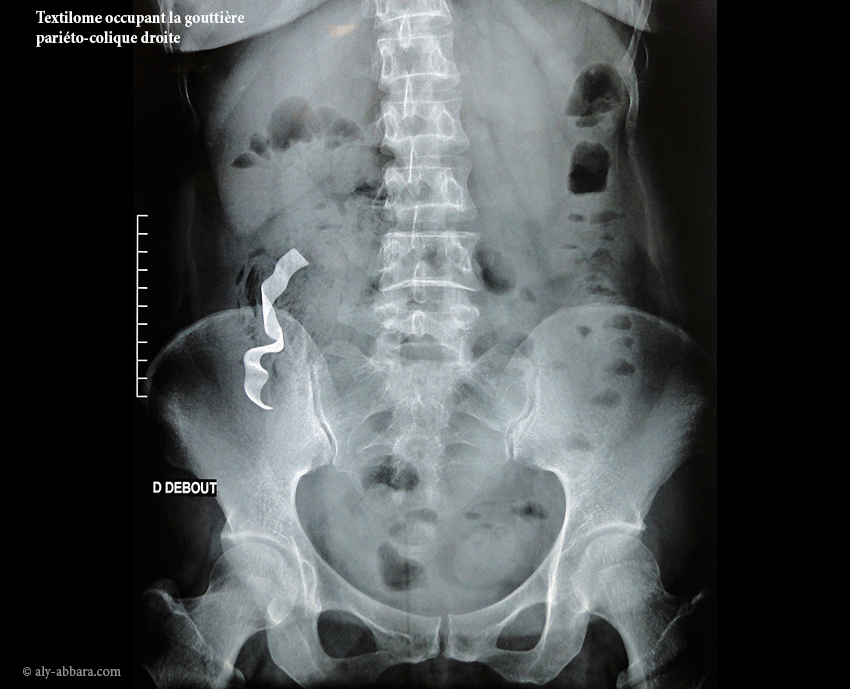

La mise en évidence de la bande radio-opaque du dispositif médical chirurgical

• Radiologiquement, le cliché d'abdomen sans préparation est peu contributif sauf quand il s'agit d'un corps étranger marqué, partiellement radio-opaque afin de faciliter sa détection sur les radiographies standard et les images de scanner.